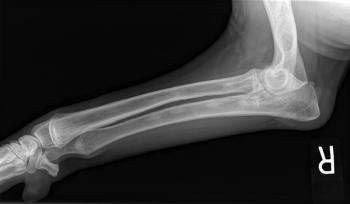

Appropriate management can help control the clinical signs and improve equine quality of life

Part I of a series: nonsurgical diseases

Screening test offers preventive approach to address this debilitating disease